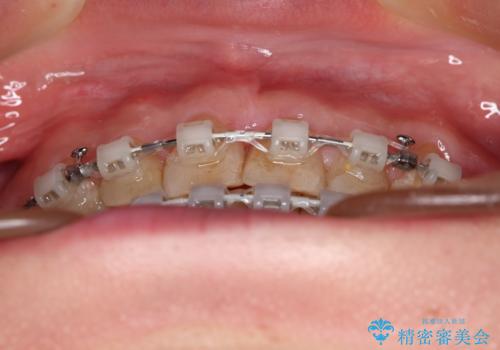

- 矯正装置

- 審美装置

- 1年4ヶ月

- 10-30回

前歯に隙間がいくつかあったため、今回は上下でゴムかけを行いスペースを埋めるための力をかけて閉じました。もう少し早く終了する予定でしたが、ブラッシング不良による歯肉腫脹があり、一部スペースクローズに時間がかかりました。